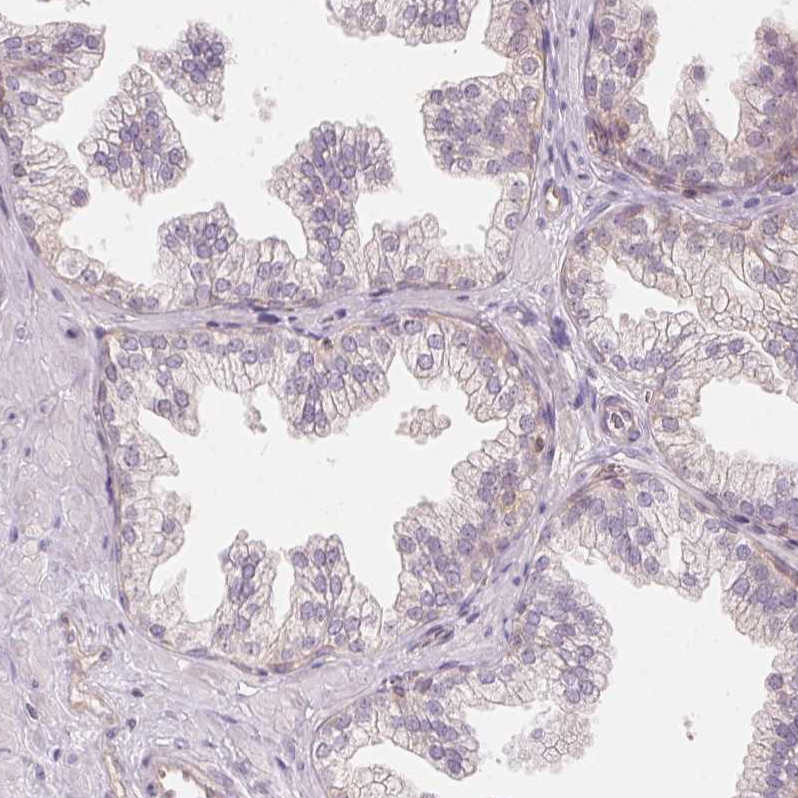

Immunohistochemistry analysis in human skin and liver tissues using HPA064307 antibody. Corresponding BLMH RNA-seq data are presented for the same tissues.